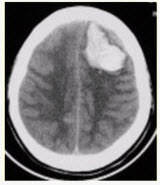

患者男,45岁,突发剧烈头痛伴呕吐30min。既往有高血压病史,平日血压为(190~160)/(100~110)mmHg。查体:右侧肢体肌力Ⅱ级,无颈项强直。CT表现如下图。

A.急性脑梗死

B.急性脑血肿

C.蛛网膜下腔出血

D.脑星形细胞瘤

E.急性化脓性脑炎

关于脑血肿典型的MRI表现,描述不正确的是()

A.3d以内,T1WI等信号,T2WI低信号

B.3~6d,T1WI低信号,T2WI低信号

C.6~8d,T1WI高信号,T2WI高信号

D.15d以后,T2WI上高信号的血肿周围出现低信号环

E.完全液化后,T1WI低信号,T2WI高信号

患者男,70岁。突发昏迷。头CT显示如下图。

A.硬膜下血肿

B.正常

C.硬膜外血肿

D.脑挫裂伤

A.左侧额顶部硬膜下半月形混杂密度影

B.脑皮质未见异常

C.脑皮质受压内移

D.中线结构右移

E.脑实质异常密度影

F.右侧脑沟变窄

116、单项选择题

A.含氧血红蛋白-正铁血红蛋白-脱氧血红蛋白-含铁血黄素

B.含氧血红蛋白-脱氧血红蛋白-正铁血红蛋白-含铁血黄素

C.含氧血红蛋白-脱氧血红蛋白-含铁血黄素-正铁血红蛋白

D.含氧血红蛋白-正铁血红蛋白-含铁血黄素-脱氧血红蛋白

E.含氧血红蛋白-含铁血黄素-脱氧血红蛋白-正铁血红蛋白